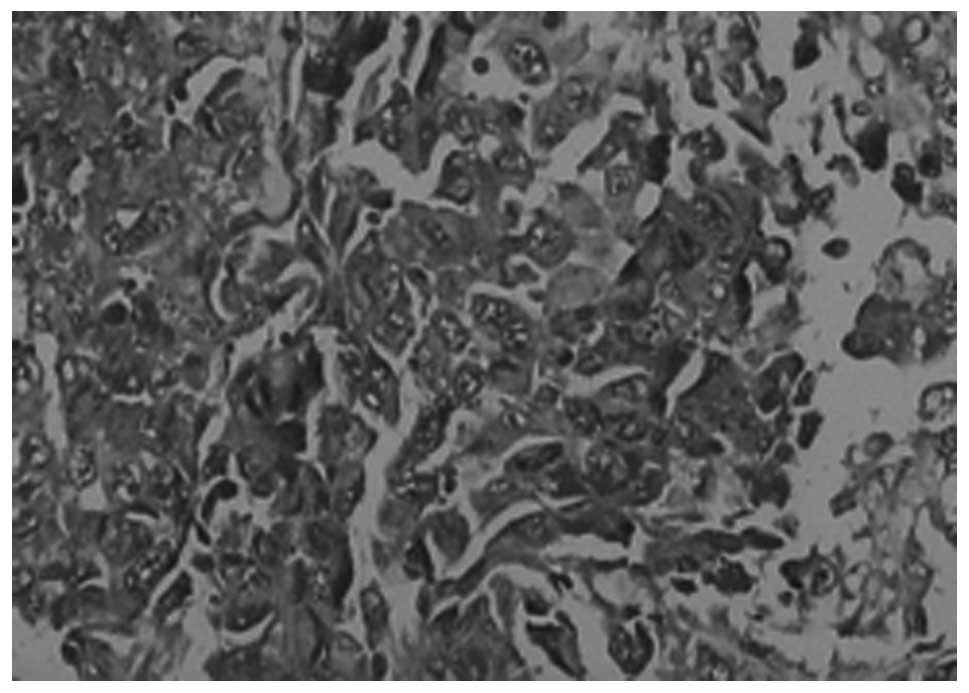

Comparison of VEGF expression in the tumor tissues between the CRC and CRC-DM groups

As shown in Table III, VEGF was primarily expressed in the cytoplasm of the tumor cells. There were varying levels of expression in the two groups, but a more evident expression was present in the CRC-DM group than in the CRC group (P<0.05; Table III, Figs. 2 and 3).

VEGF expression in a transplanted tumor of the CRC group. VEGF, vascular endothelial growth factor; CRC, colorectal cancer.

Figure 3

VEGF expression in a transplanted tumor in the CRC-DM group. VEGF, vascular endothelial growth factor; CRC, colorectal cancer.